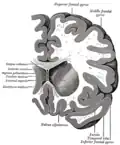

De nucleus caudatus[2] of staartkern[3] (Latijn: nucleus = kern; cauda = staart[4]) is een van de structuren van het corpus striatum in de hersenen van de mens en veel diersoorten. Lange tijd werd gedacht dat deze structuur, die deel uitmaakt van de basale kernen,[5] uitsluitend betrokken is bij de regulatie van motorische processen. De nucleus caudatus lijkt bij mensen met de ziekte van Parkinson, een bewegingsziekte, niet langer te worden geïnnerveerd door de pars compacta substantiae nigrae.[6] Uit recentelijk onderzoek blijkt echter dat de staartkern daarnaast ook een belangrijke rol speelt bij het leren en herinneren, met name voor het verwerken van terugkoppeling. Verder maakt de nucleus caudatus deel uit van het beloningssysteem van de hersenen en van de cortico–basale ganglia–thalamische lus.[5]

Anatomie

Samen met het putamen vormt de nucleus caudatus het striatum dorsale, dat functioneel als één structuur wordt gezien. Anatomisch gezien worden de twee gescheiden door een belangrijke baan van witte stof: de capsula interna. De nucleus caudatus bevindt zich in beide hersenhelften, aan de wand van de zijventrikels en schrijlings op de thalamus.[7] De boogvormige kern heeft een dikke kop en loopt steeds dunner uit in een soort staart, waaraan de structuur haar naam te danken heeft.